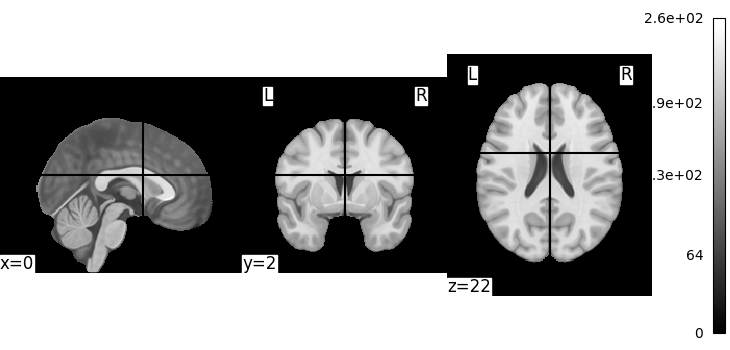

Let’s quickly plot this file:

from nilearn import plotting

plotting.plot_img(MNI152_FILE_PATH)

<nilearn.plotting.displays._slicers.OrthoSlicer object at 0x7f1f0cd664a0>

This is not a very pretty plot. We just used the simplest possible code. There is a whole section of the documentation on making prettier code.